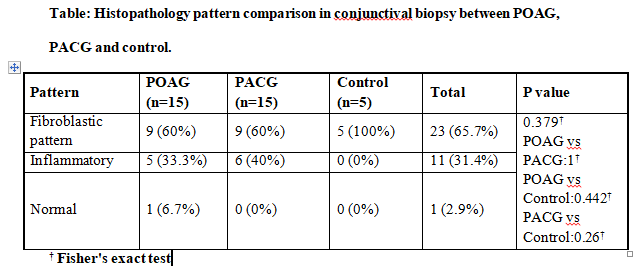

In our study conjunctival biopsy sample was evaluated. Three patterns were defined -normal, inflammatory & fibroblastic pattern.

Histopathological pattern evaluation is shown in table: